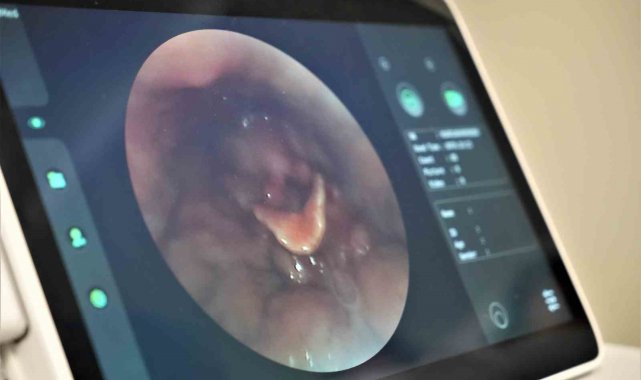

Samsun Üniversitesi Samsun Eğitim ve Araştırma Hastanesi bünyesinde hizmet vermeye başlayan Yutma Polikliniği, düzenlene törenle hizmete açıldı. 3 ay yapılan ön çalışma sonrasında Yutma Polikliniği, bölgeye hizmet verecek şekilde faaliyete geçti. Yutma problemi olan hastaların farklı doktorlar tarafından değerlendirileceği polikliniğe son teknoloji cihazlar yerleştirildi. Hastalar polikliniğe başvurarak tedavi olmaya başladı.

Yeni açılan yutma polikliniği hakkında bilgi veren Samsun Üniversitesi Tıp Fakültesi KBB Anabilim Dalı Başkanı Doç. Dr. Doğukan Özdemir, "Yaklaşık 3 aydır yaptığımız fizibilite çalışmaları sonrasında bugün itibarıyla polikliniğimizi açmış bulunmaktayız. Yutma bozukları polikliniğimiz bölgeye hizmet veriyor. Yaklaşık 5 bölüm hocası: Nöroloji, kulak burun boğaz, yutma terapisti, diyetisyen ve gastroenteroloji hocalarımızla birlikte eş zamanlı olarak hastalarımızı değerlendirip eş zamanlı tanı koyduğumuz poliklinikteyiz. Yutma bozukluğu olan farklı gruptaki hastalarımız mevcuttur. İnme hastaları, kanser hastaları, nörolojik hastalar, KBB'nin kronik hastaları gibi farklı hastalarımız mevcuttur. Bu hastalar farklı farklı bölümleri gezerek geç tanı almakta ve tedavileri çok daha geç olmaktadır. Bizim diğer yutma bozuklukları ile farkımızda burada ortaya çıkmaktadır. Türkiye'de yutma bozuklukları polikliniği halen hazırda görev yapmakta. Ancak bizim polikliniğimiz gibi örnekler Türkiye'de daha az sayıda mevcuttur. Hastalara bu konfor alanı sağlamaktadır" dedi.